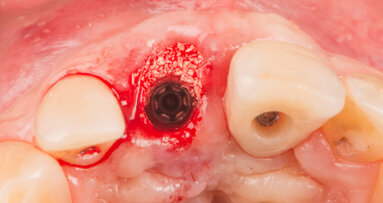

A 45-year-old female patient presented with the upper right milk canine (tooth 53) affected by caries, which caused an important occlusal and distal destruction and pulpar necrosis (Fig. 1).

Figs. 1 & 2: Initial situation: caries destruction of upper milk canine and included canine underneath.

The radiographic examination revealed an included final canine (tooth 13) and a minimum root support of the milk canine but no presence of periapical defects (Fig. 2). The patient desired a fast and aesthetic restoration of the affected tooth.

The exploration revealed a preserved buccal bone plate which allowed for the extraction of the included canine and immediate placement of a dental implant with immediate non-occlusal loading with a temporary crown, which would last for four months until the final crown would be inserted.

On the day of the surgery, the extraction of the milk and the included canines was made after an intra-sulcular palatal incision from the first upper premolar to the central incisor to allow for a good visibility of the area to treat. The extraction of the canine required a previous osteotomy and the section of the tooth. The socket walls and bone defect were debrided before initiating the drilling for the implant placement (Figs. 3 & 4).

Figs. 3–8: Extraction of the milk and the included canines (Figs. 3 & 4). Implant in final position with palatal bone grafting (Figs. 5 & 6). Impression making for the provisional restoration (Fig. 7). Provisional crown in place (Fig.8).